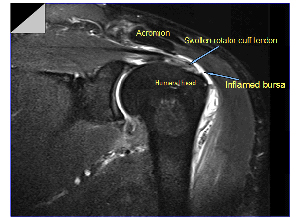

There is a lubricating sac called a bursa between the rotator cuff and the bone on top of your shoulder (acromion). The bursa allows the rotator cuff tendons to glide freely when you move your arm.

Magnetic resonance imaging (MRI) and ultrasound. These studies can create better images of soft tissues like the rotator cuff tendons. They can show fluid or inflammation in the bursa and rotator cuff. In some cases, partial tearing of the rotator cuff will be seen.